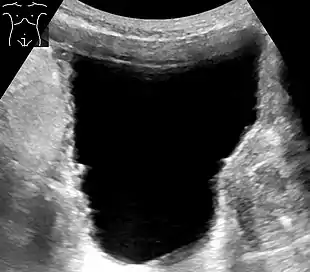

Analysis of urine flow may aid in establishing the type of micturition (urination) abnormality. Common findings, determined by ultrasound of the bladder, include a slow rate of flow, intermittent flow, and a large amount of urine retained in the bladder after urination. A normal test result should be 20-25 mL/s peak flow rate. A post-void residual urine greater than 50 ml is a significant amount of urine and increases the potential for recurring urinary tract infections. In adults older than 60 years, 50-100 ml of residual urine may remain after each voiding because of the decreased contractility of the detrusor muscle.[5] In chronic retention, ultrasound of the bladder may show massive increase in bladder capacity (normal capacity is 400-600 ml).